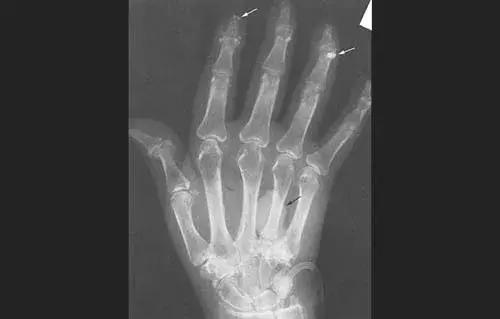

类风湿导致手掌变形、关节钙化